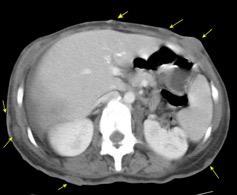

10-20% de pacientes las larvas alcanzan la circulación sistémica y pueden llegar a cualquier órgano También pueden llegar a órganos intrabdominales por migración transmural.

Yagmur Y et al. Unusual Location of Hydatid Cysts: A Case Report and Literature Review. Int Surg. 2012 / Pedrosa I et al. Hydatid disease: radiologic and pathologic features and complications . Radiographics 2000.